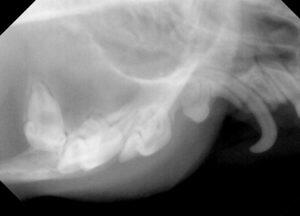

レントゲン検査では、

この様な感じです。

上顎永久犬歯は左右とも本当にありませんでした。